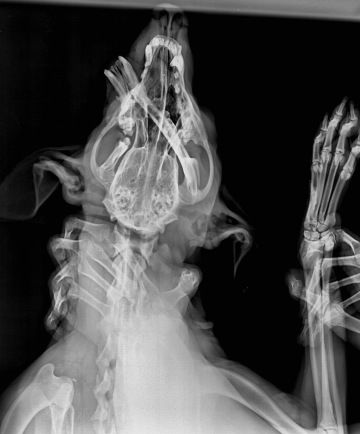

V roce 2019 strávil MVDr. Juraj Hanzel několik měsíců v Káhiře jako dobrovolník v Billy’s Veterinary Hospital, kde pracoval pod vedením MVDr. Barbory Elbadrawi Čechúrové. Už tehdy se poprvé setkal s náročnými podmínkami, ve kterých zvířata v Egyptě žijí.

Ve stejném roce a následně znovu v roce 2022 se zapojil do dobrovolnické práce v největším káhirském útulku ESMA (Egyptian Society for Mercy to Animals), který se stará o více než 2 000 zvířat – psů, koček, oslů a dalších. V roce 2022 také působil jako dobrovolník na káhirské veterinární klinice VetHouse Veterinary Center pod vedením Dr. Ahmeda Zakiho, kde pomáhal zvířatům, jež by jinak zůstala bez jakékoli péče.

Podmínky pro zvířata v Egyptě jsou extrémně drsné. Mnoho lidí žije na pokraji chudoby a zvířata přežívají na ulicích bez majitelů. Jsou často oběťmi dopravních nehod a nemají nikoho, kdo by se o ně postaral. Bohužel se jim často nedostane potřebné pomoci – a pokud ano, není to vždy v kvalitě, jakou by si zasloužila. Jejich jedinou nadějí jsou lidé, kterým jejich osud není lhostejný.

"S případy, jaké tu jsou, jsem se nikdy nesetkal. Je to pro mne dost velká škola a řeknu otevřeně, že když zvládnu tohle, tak už asi zvládnu všechno."